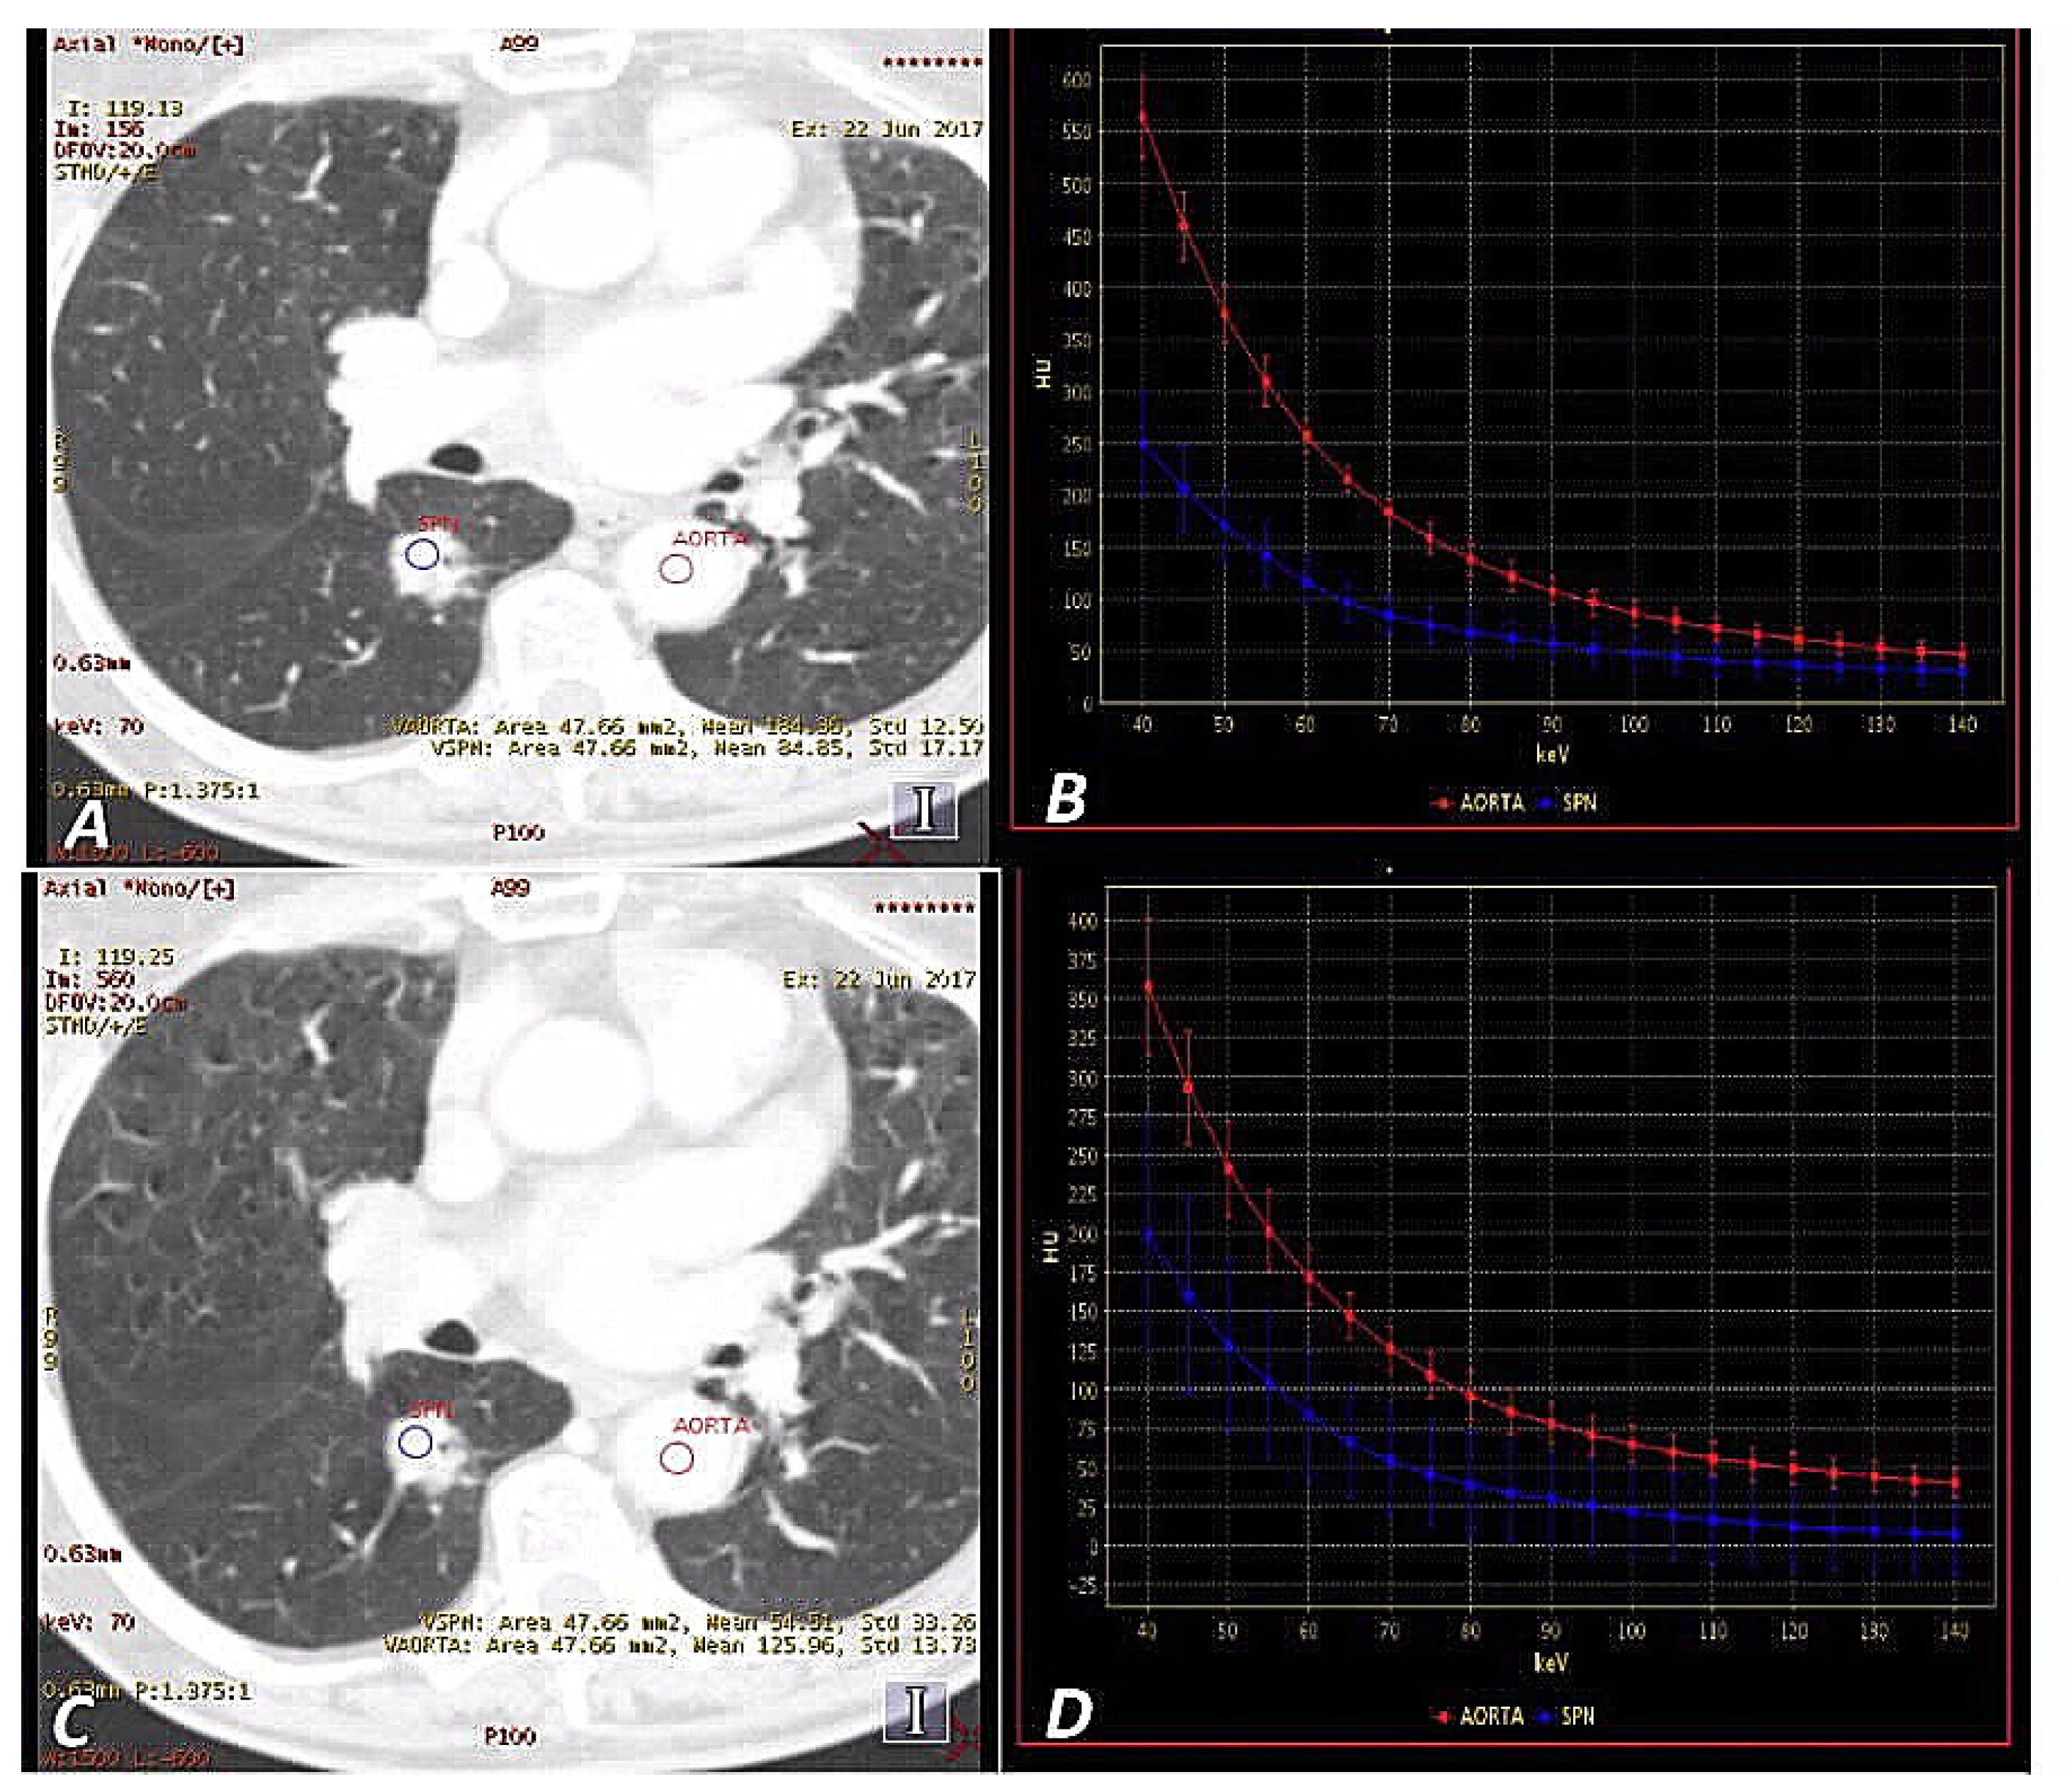

3.4. Results of the VMS Analysis

3.5. Results of the IC Map Analyses